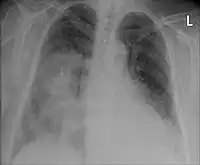

La neumonía se diagnostica con una combinación de la clínica que presenta el afectado, incluyendo tos, fiebre y dificultad respiratoria y confirmada por la consolidación pulmonar observable en una radiografía de tórax. La etiología se establece con cultivo bacteriológico del esputo y de la sangre (hemocultivo). A menudo una broncoscopia es indicada para ciertos pacientes hospitalizados.[9] El diagnóstico acertado puede ser difícil en pacientes con otras enfermedades. Ocasionalmente se emplea la tomografía y otros exámenes para diferenciar una neumonía de otras enfermedades, como el cáncer de pulmón.

Un examen importante para el diagnóstico acertado de una neumonía es la radiografía de tórax, que puede mostrar áreas de opacidad (vistas como zonas blanquecinas), que representan áreas de consolidación. La neumonía no siempre se puede apreciar en una radiografía de tórax, bien porque se trate de un estadio inicial de la enfermedad o porque se halle infectada una porción de los pulmones que no se observa en una radiografía. Una radiografía puede también ser difícil de interpretar en pacientes con fibrosis pulmonar e insuficiencia cardíaca congestiva.[11] En algunos casos se amerita realizar una tomografía computarizada.